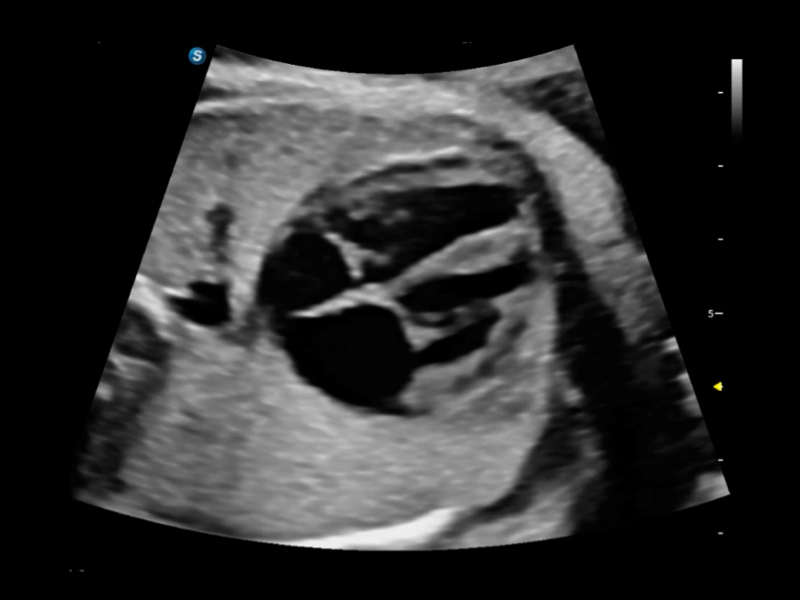

S80 提供多样化超声成像技术,可满足不同科室的需求,在助力扫查诊断和介入治疗中发挥着重要作用。